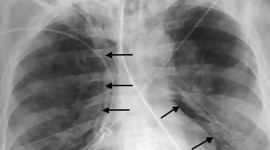

Регионалната здравна инспекция в Пловдив потвърди първи случай на ку‑треска за 2026 г. Засегнат е 67‑годишен мъж, който е приет в болница на 6 април с двойна бронхопневмония. След проведено лечение пациентът е изписан седмица по‑късно. Директорът на дирекция „Надзор на заразните болести" в РЗИ‑Пловдив д-р Милена Панайотова уточни, че подобни случаи не са нещо необичайно. По думите ѝ заболяването не е „екзотично" и не е внесено отвън, като през годините в областта са регистрирани и други инфекции. Какво представлява ку‑треската? Ку‑треската е бактериална инфекция, причинена от Coxiella burnetii. Заразяването най-често става чрез вдишване на прахови частици, съдържащи бактерията, контакт с мляко, урина, изпражнения или секрети на заразени животни (обикновено овце, кози, говеда). По-рядко заболяването се предава чрез кърлежи. Инкубационният период е между 9 и 40 дни. Хората са силно чувствителни към инфекцията и дори малък брой бактерии могат да доведат до заболяване.